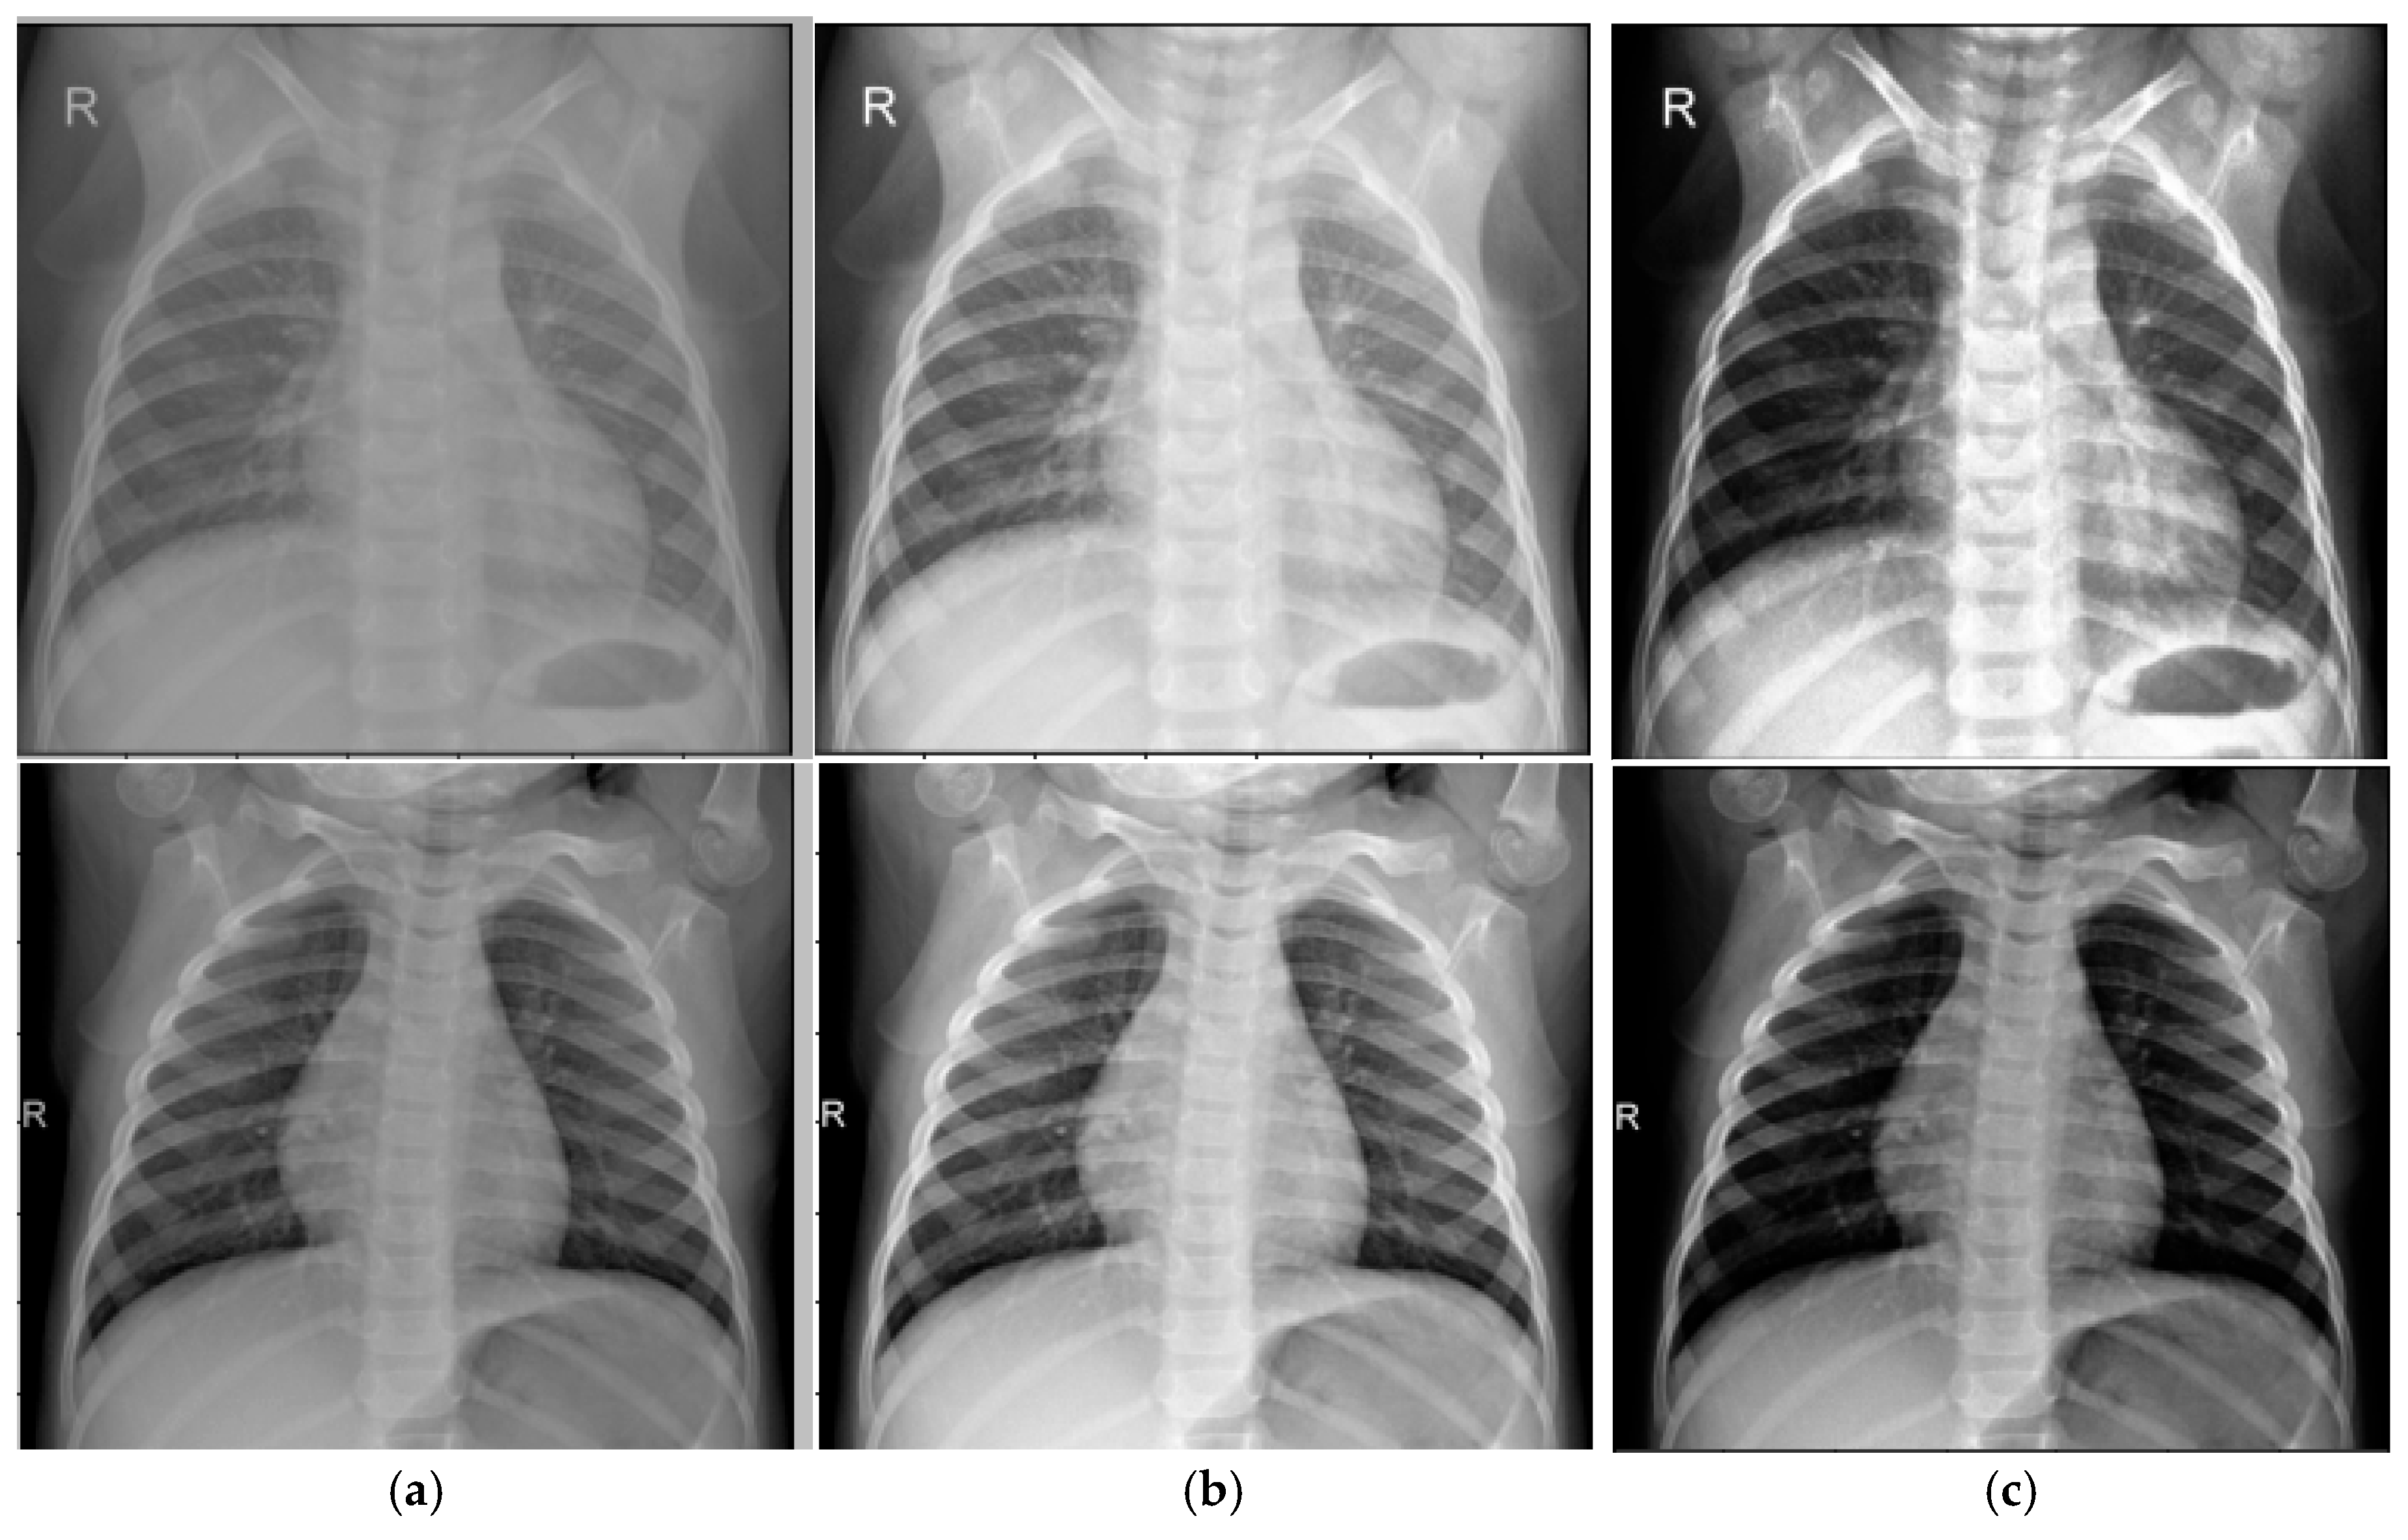

- Original image-based CNN: This model was trained on the original, unprocessed chest X-ray dataset.

- Traditional CLAHE image-based CNN: This model utilized a dataset enhanced using the traditional CLAHE algorithm.

- Modified CLAHE image-based CNN: This model employed a dataset processed with the proposed modified CLAHE algorithm.